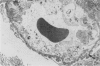

Rabbits given acute serum sickness (ASS) and treated with cyclosporin A (CyA) developed glomerular capillary thrombosis and cortical infarction, lesions not seen in unmodified ASS. Thirty-three NZW rabbits received a single intravenous injection of 250 mg/kg bovine serum albumen (BSA) with or without endotoxin (5 micrograms/kg) on day 0. Groups of rabbits were given intramuscular CyA as follows: 15 mg/kg from day -2 to +8, or 25 mg/kg/day from day -20 to +3 or day 0 to 5. Signs of this renal injury were haematuria, transient proteinuria, glycosuria and oliguria and they occurred during the rapid phase of antigen elimination when immune complexes were being formed. Seventeen of the 33 rabbits developed glomerular capillary thrombi and 11 of 17 also had glomerular and tubular infarction. Electron microscopic examination showed that these lesions were associated with severe endothelial injury and platelet-fibrin-leucocyte thrombi. These changes were more severe in the groups given 25 mg/kg. The lesions were not seen in untreated rabbits and ASS, nor in normal rabbits given equivalent doses of CyA alone. A strikingly similar renal lesion has been seen in patients receiving CyA following bone marrow transplantation, and also in the haemolytic uraemic syndrome. The model we describe may be valuable for the study of the mechanisms of endothelial injury and thrombosis in the kidney.